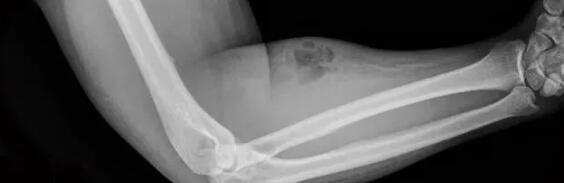

一名33岁的爱尔兰男子因为举重物时下背疼痛住进了都柏林医院。在医院检查时,医生发现他的右下臂红肿且有相当严重的皮下感染迹象,X光片也显示皮肤深层有脓肿发生。